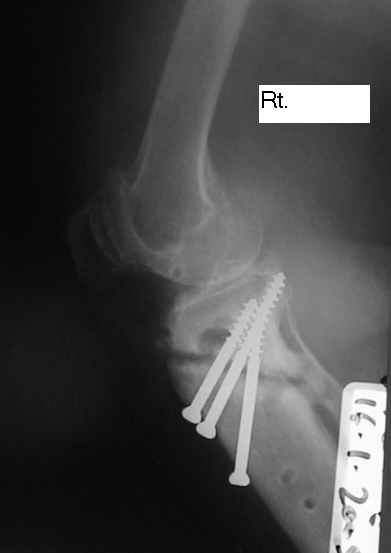

Dorogie Kollegy,Ko mne obratilas' bol'najia, ei 64 goda, ona stradaet ot dvuhstoronnego varusnogo gonoartroza, ei bila vipolnena Visokajia Ostotomjia goleny sprava 01.06.2004, zona osteotomii ne sroslas', plastina bila udalena 12.09.2004 (vidimo iz-za ee nestabilnosti), zona osteotomii tibia bila fixirovana 3-mjia shurupami. Seachas sylno bespokoyat boly v dvuh sustavah, hodit s trudom s pomoshyu Walker, a voobshe ona seachas na invalidnoi kolyaske. Podzkazite, pozhalusta, kak mozno ei pomoch' (snimky prilagayutsa)

Уважаемый Dr.Castro. Мне кажется возможной причиной несращения перелома явилось затекание синовиальной жидкости в зону остеотомии. Проксимальный фрагмент б.берцовой кости мал и "неудобен" для фиксации. Как вариант - можно предложить ЧКДО по Илизарову с временной фиксацией н.з бедра с целью усиления стабильности.Но с аппаратом придется повозиться ( поиграть фрагментами голени).Если нет возможности или желания заниматься аппаратом, придется выполнить СТАБИЛЬНЫЙ остеосинтез мыщелковой или г-образной пластиной, но обязательно с аутопластикой области несращения. Или в виде аутокрошки, или путем перемещения костного трансплантата с дистального фрагмента б.берцовой кости кверху с перекрытием области несращения.

Уважаемый Dr.Castro, я абсолютно согласен с коллегой на счет первого варианта. Использовать пластину с угловой стабильностью не советую поскольку у нас были случаи несращения в этой области при использовании Г-образных пластин после первичного остеосинтеза.В даном случае нужна постоянная и мощная компресия которую можно достичь только методом Илизарова.

U bol'nogo non-union osteotomii tibii. V vozraste 64 let, sdelal bi sleduiezhee:

Work out, proverit', net li infection: ESR, CRP, White cell Scan. Esli infection net togda est' dva varianta:

1. I predpochel bi ego: Total Knee Arthroplasty. Nuzhen budet Revision ( Long stem) tibial Component.

2. Ne sovetuiu delat' geroicheskix postumkov v otnoshenii Non union. Tut est' mnogo problem, ved' esteotomia provedena ne pravili'no s tochki zrenia deformazii. Orientazia ploskosto kollennogo sustava xotia ne ploxa v sagital'noii ploskosti, no vo frontl'noi idet sil;noie otklonenie narozhu i vniz. A nam tida ne nado.

Было бы логично удалить шурупы и выполнить остеосинтез голени апп. Илизарова. Аппарат из трех опор. На проксим. отломок одна опора и вней 4-5-6 спиц из которых 2-3 с напайками. А на дист. отломок 2 опоры: на уровне прксим. конца 2 спиц с напайками, на уровне дист. метафиза 3 спицы.

Компрессию создавать через балку по передней поверхности во встречно-боковом направлении в сагитальной плоскости по 1 мм в сутки 10-15 дней.Затем перейти на поддерживающую компрессию как во встречно-боковом направлении, так и по оси.